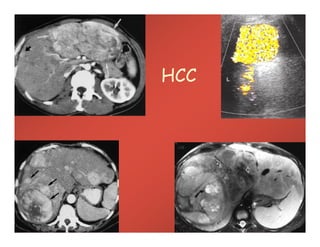

HCC